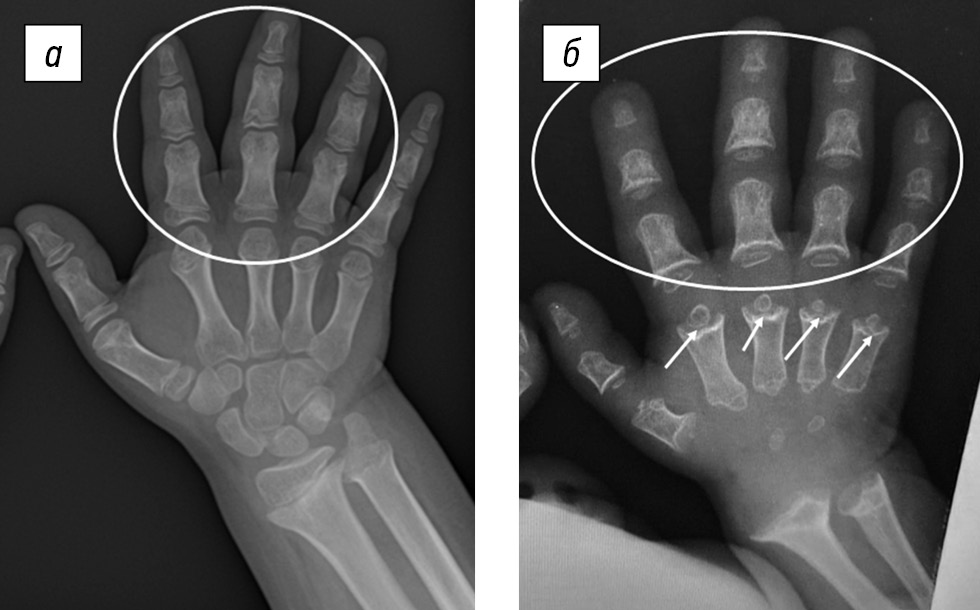

Диагностике ПСАХ в значительной степени способствовал анализ рентгенологических данных, в результате которого обнаруживали специфические изменения в виде задержки оссификации апофизов тел позвонков в детском возрасте, что определяло их характерную клювовидную форму на рентгенограммах позвоночника в боковой проекции, а также укорочение трубчатых костей с генерализованной задержкой оссификации эпифизов, проявляющейся уменьшением их размера, неправильной формой, неровными контурами. Кроме того, типичным было выраженное вовлечение метафизов в виде их расширения с неровностью (волнистостью и «изъеденностью») контуров. На рентгенограммах кистей наблюдали характерную картину в виде укорочения пястных костей с чашеобразно расширенными метафизами и маленькими округлыми эпифизами по типу «шарика в гнезде» (ball-in-socket) [18] (рис. 5).

Рис. 5. Рентгенограмма кистей пациента с ахондроплазией (а) и псевдоахондроплазией (б): умеренная ульнарная девиация кисти и брахидактилия у обоих пациентов (отмечено белым контуром); укорочение пястных костей с чашеобразно расширенными метафизами и маленькими округлыми эпифизами по типу «шарика в гнезде» (ball-in-socket) у пациентов с псевдоахондроплазией (белые стрелки)